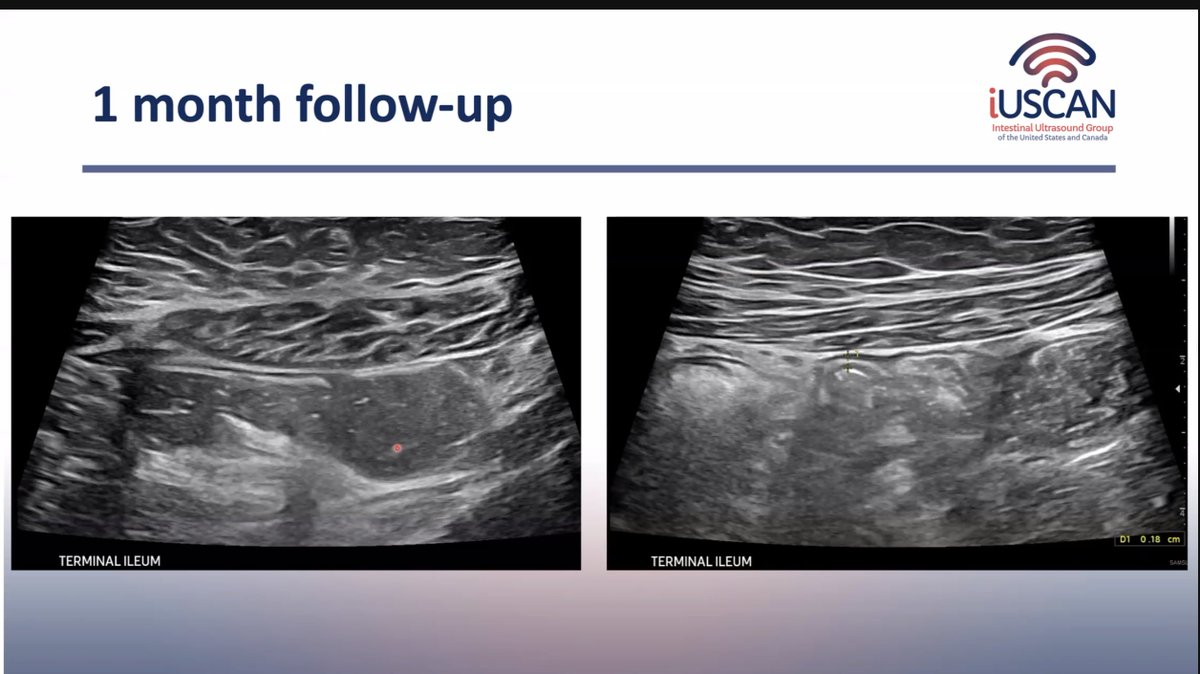

IUSMonthly continues through the summer months! Thanks to @MaiaKayalMD & @KrugCleveland for presenting on the use of #IUS in pregnant #IBD patients and @DrMikeDolinger for updating us on his previous pediatric #ASUC case. See you next on August 8th!

Fantastic cases yesterday from @yusukemiya73 on how #IUS identified the need for dilation in a patient with obstruction and @drhughiefraser who showed that IUS predicts risk of flare despite improved symptoms (and can be helpful in non-compliant patients!)